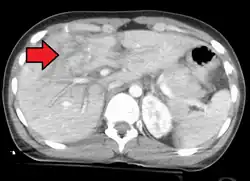

Grade 4 liver laceration

Isoliert_intraparenchymatoese_Leberruptur_24M_-_CT_KM_-_001

Imaging, such as the use of ultrasound or a computed tomography scan, is the generally preferred way of diagnosis as it is more accurate and is sensitive to bleeding, however; due to logistics this is not always possible.[6] For a person who is hemodynamically unstable a focused assessment with sonography for trauma (FAST) scan may take place which is used to find free floating fluid in the right upper quadrant and left lower quadrant of the abdomen. The FAST scan however may not be indicated in those who are obese and those with subcutaneous emphysema.[7] Its speed and sensitivity to injuries resulting in 400mL of free-floating fluid make it a valuable tool in the evaluation of unstable persons. Computed tomography is another diagnostic study which can be performed, but typically is only used in those who are hemodynamically stable.[7] A physical examination may be used but is typically inaccurate in blunt trauma, unlike in penetrating trauma where the trajectory the projectile took can be followed digitally.[8] A diagnostic peritoneal lavage (DPL) may also be utilized but has limited application as it is hard to determine the origin of the bleeding.[9] A diagnostic peritoneal lavage is generally discouraged when FAST is available as it is invasive and non-specific.[7]